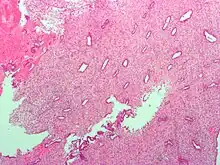

Low magnification micrograph of decidualized endometrium. H&E stain

(B) secretory endometrium (Left: HE × 10) and secretory endometrial cells (Right: HE × 10)